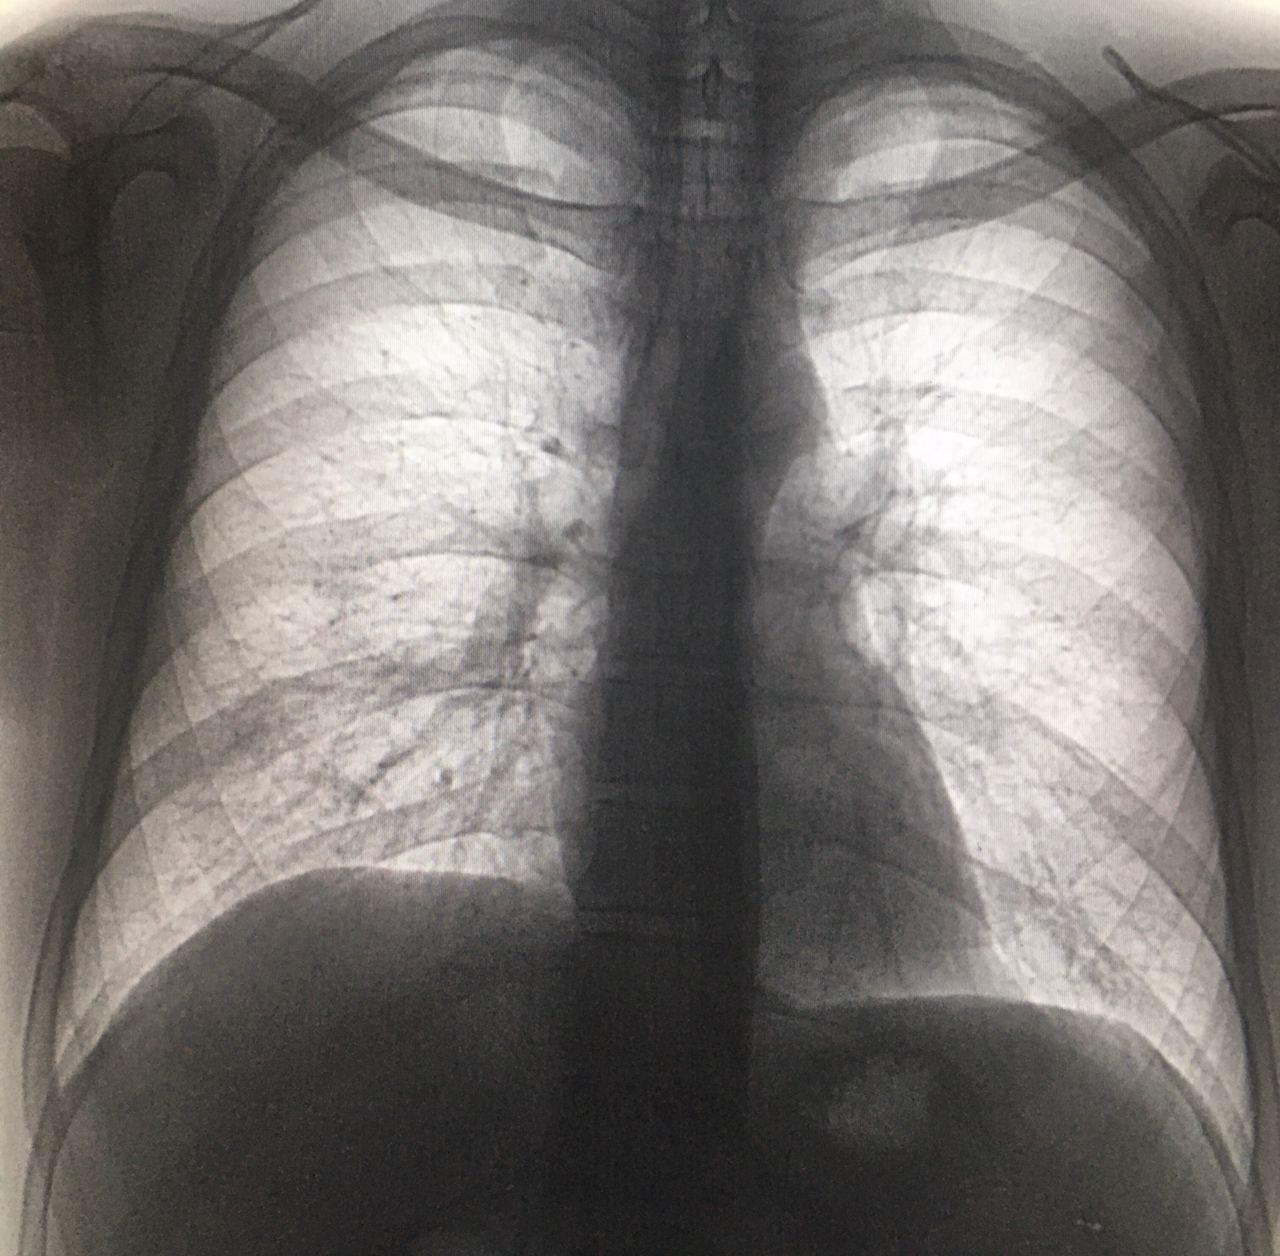

Мужчина, 1987 года рождения. Профилактическая ФЛГ, пациента не видела. Архива нет. Справа не нравится в нижних отделах, может быть пневмония? Посмотрите, пожалуйста 🙏🏻

Перибронхиальная инфильтрация вроде